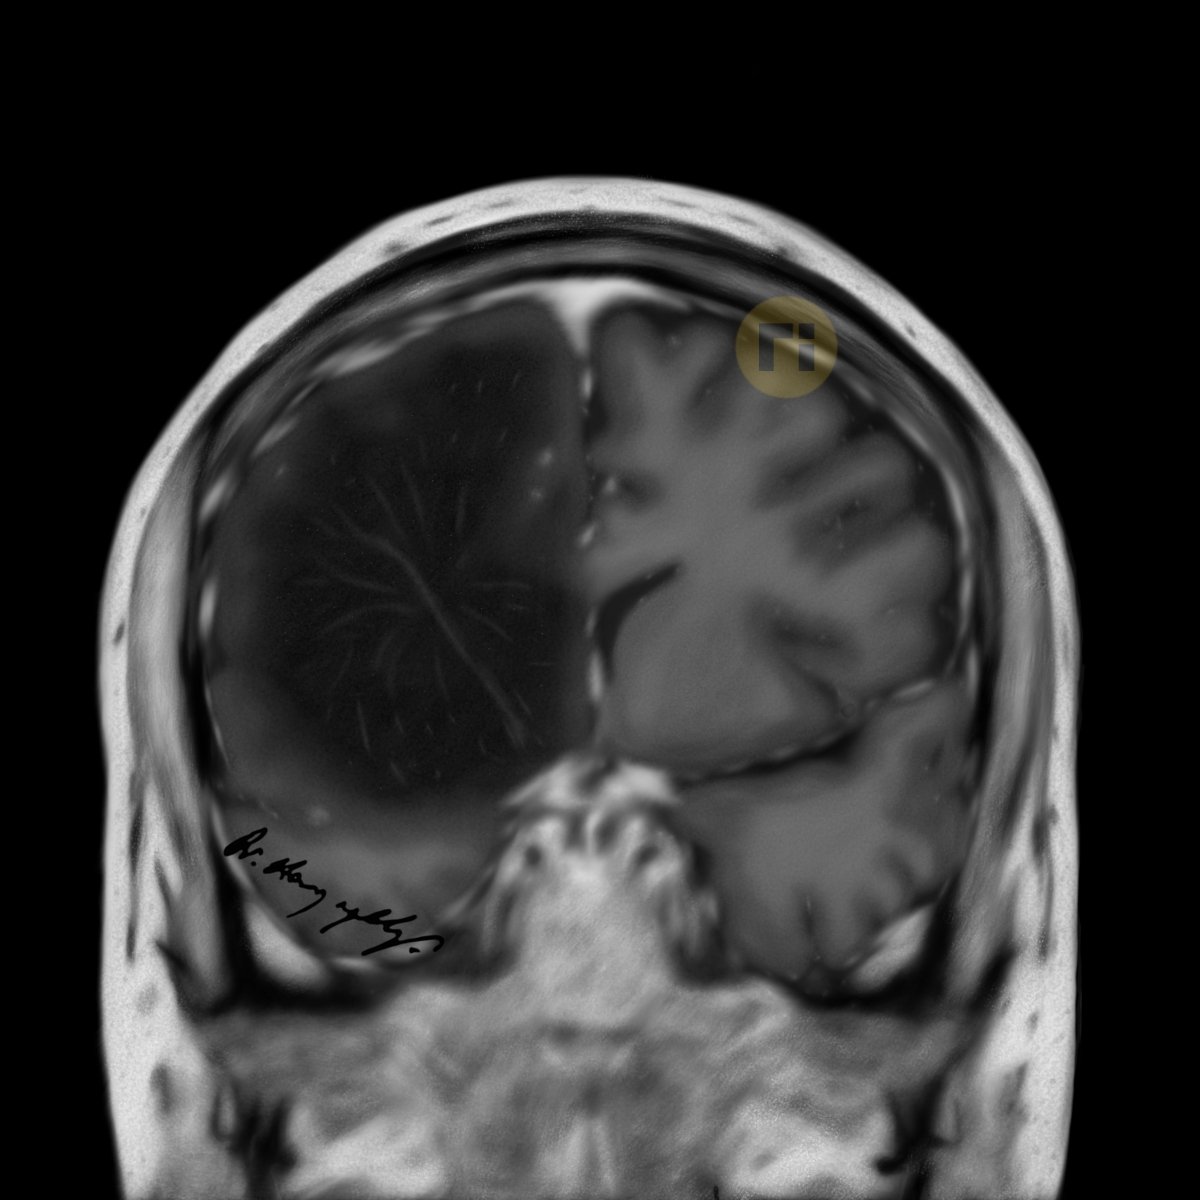

QUCARILL ♠️♦️♣️♥️ Labrune syndrome (Leukoencephalopathy with cerebral calcifications and cyst) vs L-2-hydroxyglutaric aciduria and Brain Tumour #radiologicalillustration ✍️ pixel by pixel handmade!

Fresh! 👍♥️🙋‍♂️ Imaging patterns of paediatric CNS mitochondrial disorders https://t.co/M3ohYWjbLW #radiologicalillustration ✍️ pixel by pixel handmade!

“Fireworks Sign” Diffuse Astrocytoma (MYB or MYBL1-altered) https://t.co/oxgM0KUy5T #radiologicalillustration ✍️ pixel by pixel handmade!